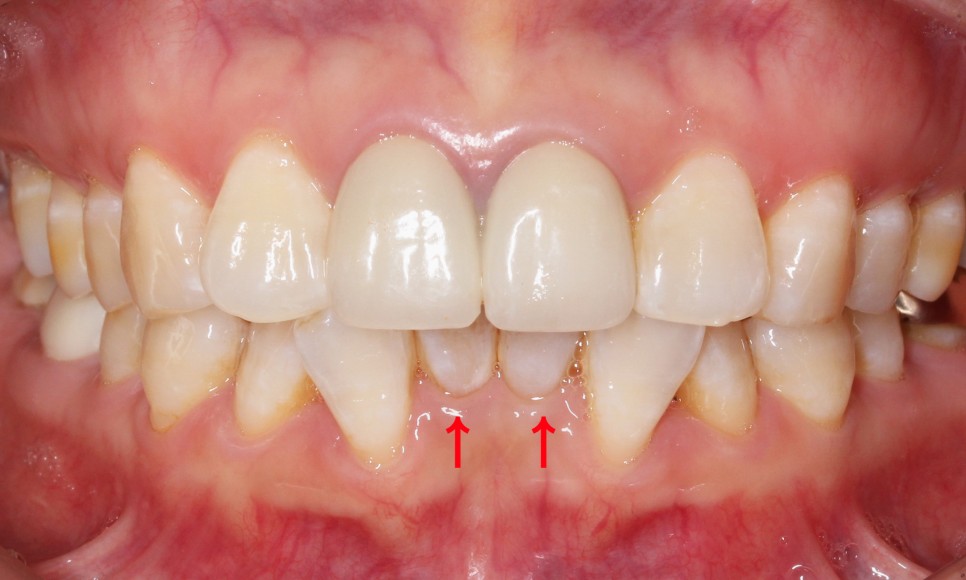

전체적인 아랫니의 치열도

심하게 삐뚤거렸던

처음의 모습과는 달리

아랫니 부분교정 (2D교정) 으로

이상적인 치아의 배열인

U자 곡선의 형태로

바뀌었습니다.